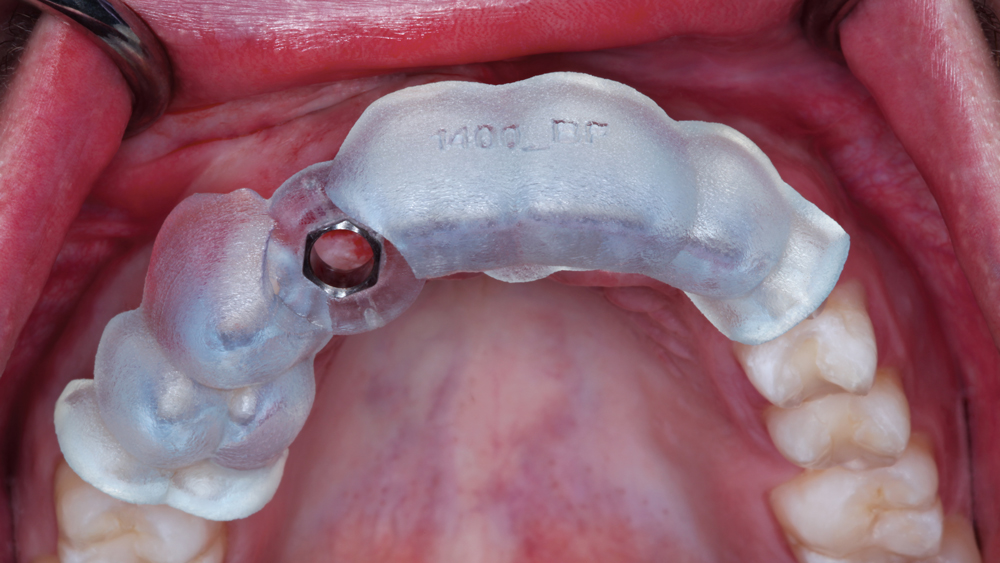

The Hahn Guided Surgical Kit (Glidewell Direct) has been designed to eliminate the need for drill keys, inserts or “spoons” commonly found in other guided surgery systems. The surgical kit’s efficient, straightforward sequence of drills creates an osteotomy in the exact shape, diameter and length of the prescribed implant, ensuring the implant ends up in the exact position determined by the digital treatment plan. Further, the entire surgical procedure, from the initial osteotomy to implant placement, is performed through the surgical guide. Whether using the Digital Treatment Planning service of Glidewell Laboratories or another source for surgical guides, specific guide sleeves are provided to enable practitioners to perform the entire surgical procedure with an efficient and fully guided protocol.

The following case illustrates the efficient, straightforward clinical workflow for placing Hahn Tapered Implants via guided surgery. A digital treatment plan is developed in which a 3.5 mm implant is positioned to support the ideal prosthetic outcome. An immediate provisional crown is designed in concert with the surgical guide and delivered at the time of surgery, helping to produce a predictable, highly esthetic restoration for a demanding case in the smile zone.